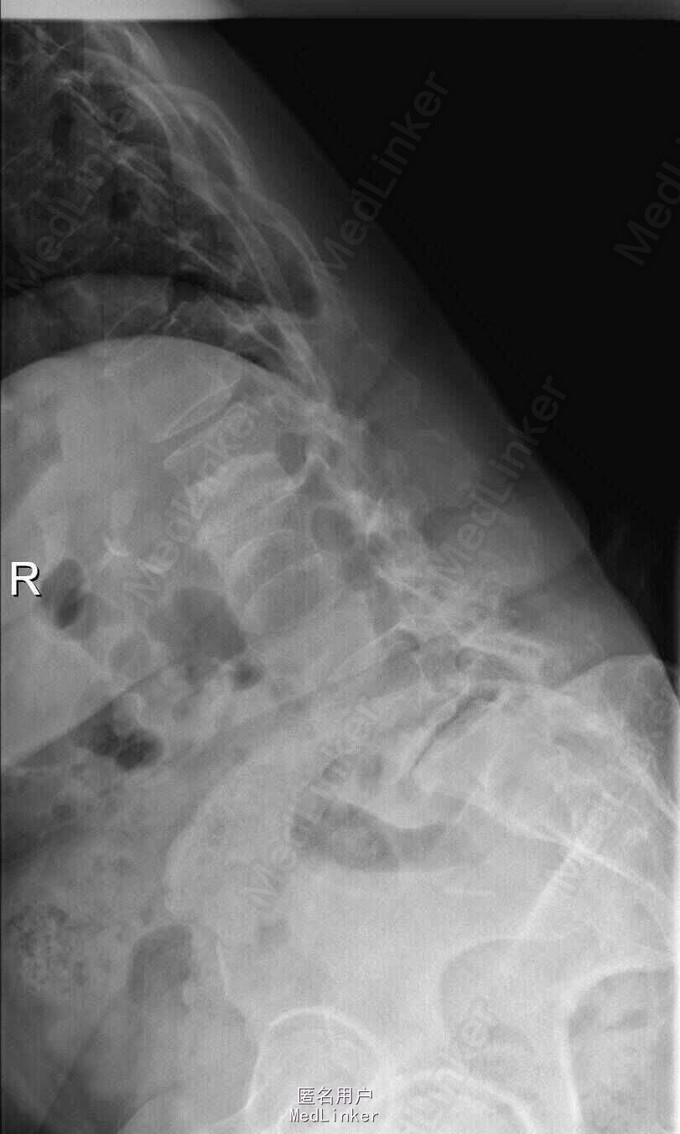

主诉:右下肢麻木伴驼背11年余 病史:患者女性,64岁,11年前无明显诱因出现右下肢疼痛,休息后好转。未予重视,后出现右下肢麻木感,逐渐小狐仙右臀部坚硬,驼背,伴跛行。常感双腿酸胀,腰部疼痛。自行步行距离小于200米,即会发生右下肢僵硬,麻木疼痛。X线检查示腰椎侧弯

查体:脊柱侧弯,上肢无麻木,疼痛感觉异常,腰部右侧疼痛,右下肢及右臀部疼痛,麻木感。双侧肌力及肌张力可,膝腱反射(+),踝反射(+),病理征(—),直腿抬高试验。右侧40度,左侧55度。 辅助检查:腰椎x线片:腰椎侧弯,腰椎退行性改变,L5椎体略行前滑脱 脊柱全长:胸腰段呈S形,L5椎体向前滑脱,L3椎体略变扁,颈胸腰椎退行性改变 MRI:脊柱侧弯,L2-3,L3-L4,L4-L5,L5-S1椎间盘突出,相应节段椎管狭窄